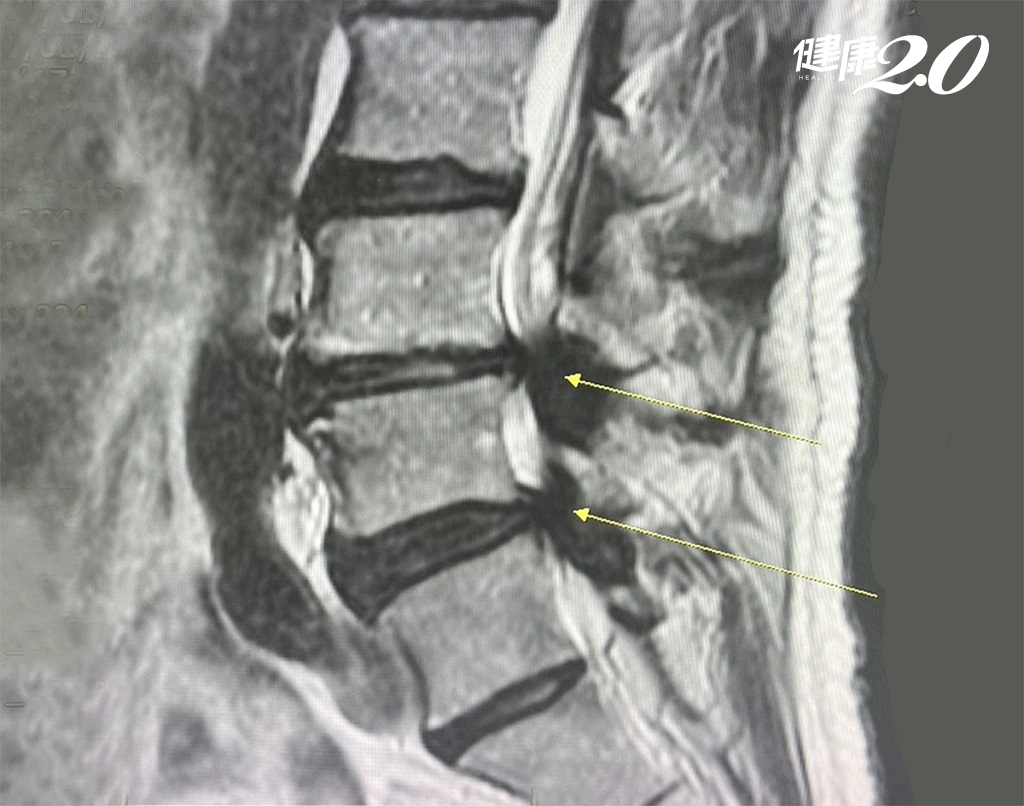

李先生回憶,十幾年前他開始感覺右腳麻痺,經過多次脊椎牽引和腰部拉伸治療後,症狀逐漸轉移到左腳,直到半年前,腰部以下的全部感覺都變得麻木。他經過網路查詢後懷疑自己可能罹患馬尾症候群,因而趕緊前往醫院進行核磁共振檢查。李先生原先考慮骨釘及支架,但因為不安心,後來調閱資料後,發現近兩三年來內視鏡手術是一種較為安全且風險低的選擇,住院時間也相對較短。

鍾玉軒醫師指出,李先生因為第三、四、五節脊椎狹窄病變,退化造成骨頭、韌帶增生,而讓腔式變窄,這是中高齡者常見的退化疾病,退化狹窄會直接壓迫腰椎或薦椎的神經根,進而引起發炎導致麻痛,連如廁都相當不便,像是排尿的時候會感覺不到,符合馬尾症候群的壓迫症狀。

雖然李先生退化情況拖延相當多年,嘗試各種保守治療無效,但評估其狀況尚不需打骨釘治療,建議他施行微創脊椎內視鏡減壓手術治療,術後只留下2個0.5公分小傷口,讓連打針也恐懼的李先生不需承受大傷口或多道傷口的疼痛。

而李先生的手術內容為第三、四腰椎跟第四、第五腰椎,總共兩節的脊椎內視鏡減壓手術,主要是移除壓迫在神經上面肥厚的黃韌帶以及增生的骨刺,並沒有去移除椎間盤。此為脊椎內視鏡部分(單側)椎板切除手術,雙側黃韌帶移除手術。